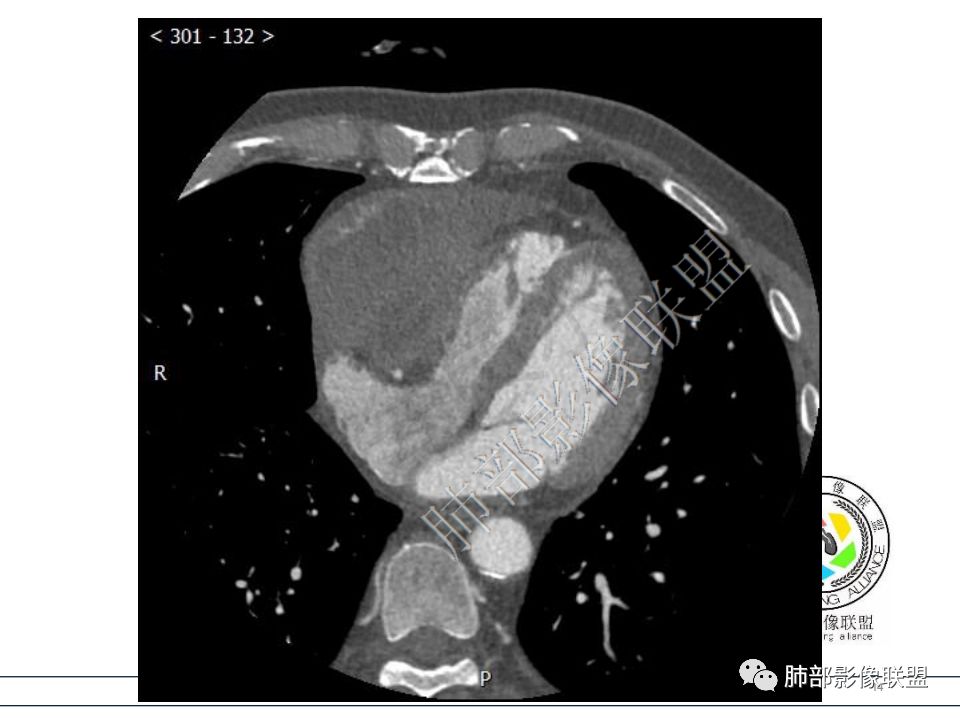

定位心包,形态不规整,结节状突起,与心脏界限模糊,考虑心包间皮瘤。 医学百科网 | YxBaike.Com

心包结节状增厚,右房室受压,考虑心包转移瘤? 医学百科网 | YxBaike.Com

病例3 心包肿块,向心包内外生长,可见类似胸膜尾征,右心室受压变形,心包积液病史,恶性间皮瘤,鉴别转移瘤。

脂肪间隙消失,临近心包增厚,定位心包,定性恶性。 医学百科网 | YxBaike.Com

右室受压,但是脂肪间隙消失,跟第一例完全不同。

恶性的大家都没问题,不统一的是恶性间皮瘤还是转移瘤。 医学百科网 | YxBaike.Com

转移瘤一般侵犯心包局部同时累及心肌,心包积液量一般没有恶性间皮瘤大。

恶性间皮瘤肿瘤脱落在心包内转移,病变多发,大量心包积液。

符合恶性间皮瘤,肿瘤侵及右侧心室肌壁。